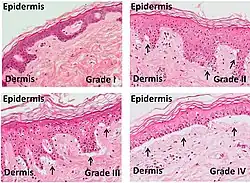

In the clinical setting, graft-versus-host-disease is divided into acute and chronic forms, and scored or graded on the basis of the tissue affected and the severity of the reaction.[2][3]

Acute GvHD is staged as follows: overall grade (skin-liver-gut) with each organ staged individually from a low of 1 to a high of 4. Patients with grade IV GvHD usually have a poor prognosis. If the GvHD is severe and requires intense immunosuppression involving steroids and additional agents to get under control, the patient may develop severe infections[14] as a result of the immunosuppression and may die of infection. However, a 2016 study found that the prognosis for patients with grade IV GvHD has improved in recent years.[15]